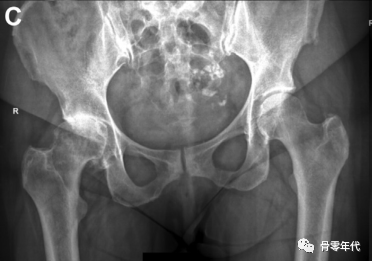

(A)内收和内旋对右髋关节偏移量的影响。与左侧臀部相比,这会产生一种减少偏移量的感觉。(B)骨盆倾斜对肢体长度和偏移量的影响,通过减小髋关节抬高时的偏移量和肢体长度,而对向下旋转的髋关节产生相反的影响。